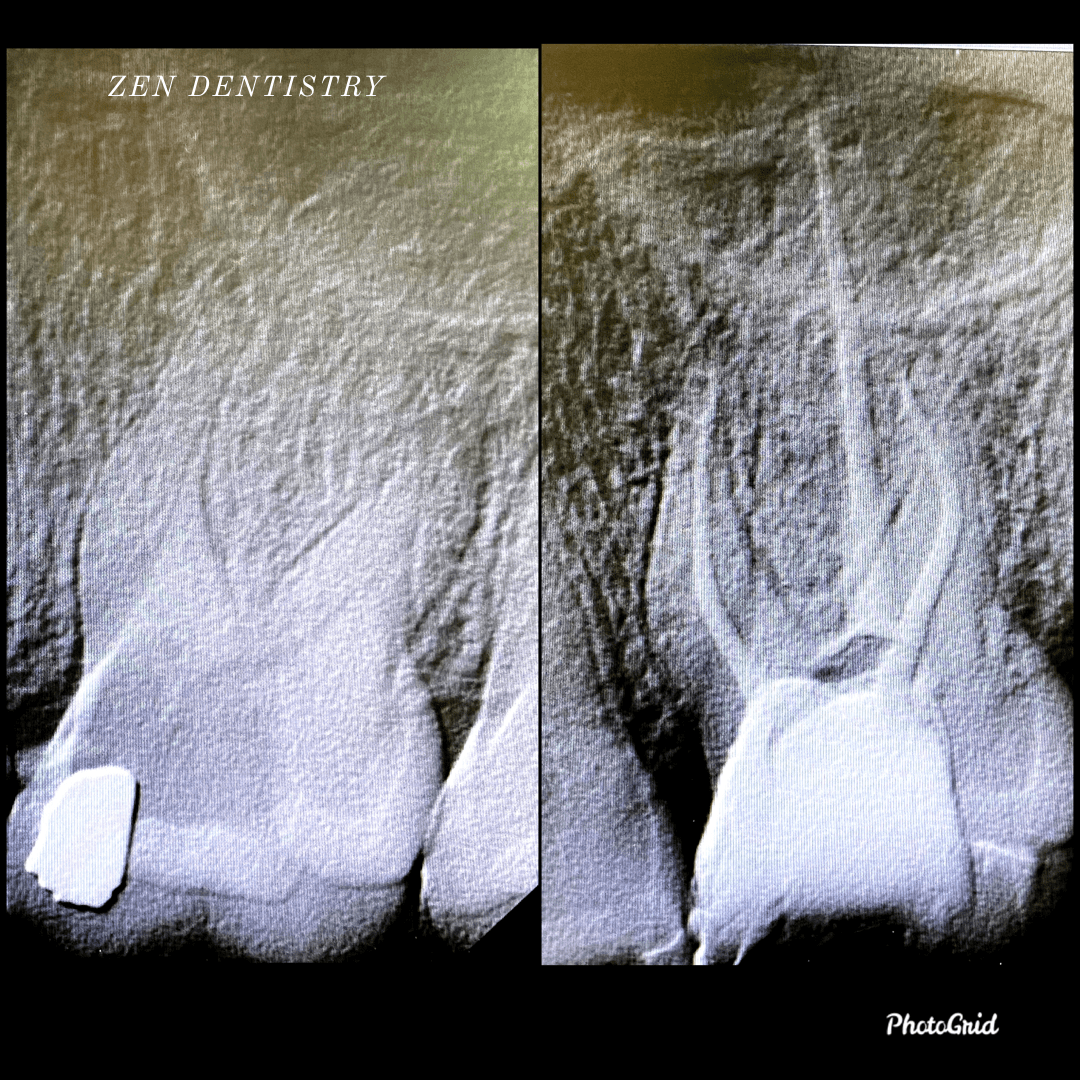

Patient presented to the A thorough clinical exam, endodontic screening and proper x rays led to the diagnosis of irreversible pulpitis(inflamed pulp tissue) due to secondary dental caries with inflamed periodontal ligaments.